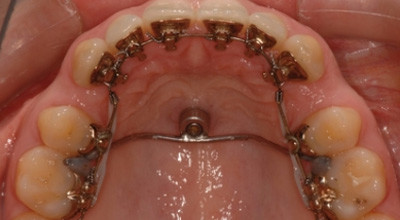

Moderne kieferorthopädische Apparaturen erwecken den Eindruck, dass eine Behandlung in die Hände des Systems übergeben werden kann und sich der Praktiker auf ein Labor-Set-up verlässt, das am Patienten gar nicht umgesetzt werden kann. Dieses Problem ist bei der Lingualtechnik genauso präsent wie bei selbstligierenden Brackets oder Alignersystemen. Der Einsatz von skelettalen Verankerungen (TAD) erweckt den trügerischen Eindruck, jede Zahnbewegung werde berechenbar und es könne auf die Mitarbeit des Patienten in der heutigen Kieferorthopädie verzichtet werden. Der Einfluss auf Entscheidungen, wie eine Behandlung aussehen soll, ist nur zum kleinen Teil von der Technik abhängig als von Biologie, Befund und Diag­nose. Der Einsatz von ossären Verankerungssystemen in jeder Technik erweitert unser Spektrum enorm und ist in der Lingualtechnik genauso anwendbar wie labial. Die folgenden Beispiele (Abb. 1 bis 8) sollen die Vielfalt an Anwendungsmöglichkeiten zeigen. Das Gaumenimplantat steht außerhalb der Zahnreihe und kann rotationsstabil belastet werden – alles Vorteile, die ein Anpassen an die sich ändernden Verankerungsan­sprüche im Verlauf jeder Behandlung möglich machen.

Die Kraftübertragung erfolgt entweder direkt oder indirekt über eine individuell im Labor hergestellte Suprastruktur (Abb. 10). Der Hauptvorteil liegt darin, dass während der Belastung jederzeit die Richtung der applizierten Kraft verändert werden kann. Die Kraftübertragung erfolgt über Teilbögen.

Der Hersteller bietet seit Neuestem auch eine vorgefertigte Lösung an, die direkt am Patienten nur noch adjustiert werden muss und direkt an einen gewünschten Zahn mit­tels Adhäsivtechnik befestigt wird. Bei dieser Lösung ist aber nur eine indirekte Belastung möglich, was den Einsatz etwas einschränkt. Bei der indirekten Belastung werden Ankerzähne gegen das Implantat stabilisiert und können somit als Verankerungseinheit mit sehr hoher Resistenz dienen. Bei der direkten Gaumen­implantat-Belastung wirkt direkt eine Kraft zwischen einem Zahn und dem Implantat. Die aktiven Bewegungen können einerseits mit sagittal voraktivierten Delta-Loops oder mit einem straight wire und push-/pull coils durchgeführt werden. Bei der Straight-Wire-Technik empfiehlt es sich, einen Stopp beim distalen Ende einzubiegen resp. anzubringen, um ein freies sagittales Gleiten des Drahtes zu vermeiden. Bei der beschriebenen Suprastruktur ist ein Stainless-Steal-Draht der Dimension von .018'' x .025'' ideal für beide Behandlungsansätze.